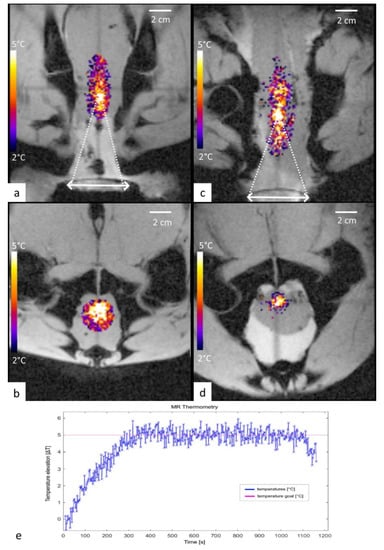

3.2. Performance Test in Tissue Mimicking Gel

3.3. Ex Vivo Test

- Guillemin, P.C.; Gui, L.; Lorton, O.; Zilli, T.; Crowe, L.A.; Desgranges, S.; Montet, X.; Terraz, S.; Miralbell, R.; Salomir, R.; et al. Mild hyperthermia by MR-guided focused ultrasound in an ex vivo model of osteolytic bone tumour: Optimization of the spatio-temporal control of the delivered temperature. J. Transl. Med. 2019, 17, 350. [Google Scholar] [CrossRef]

- Ozhinsky, E.; Salgaonkar, V.A.; Diederich, C.J.; Rieke, V. MR thermometry-guided ultrasound hyperthermia of user-defined regions using the ExAblate prostate ablation array. J. Ther. Ultrasound 2018, 6, 7. [Google Scholar] [CrossRef]